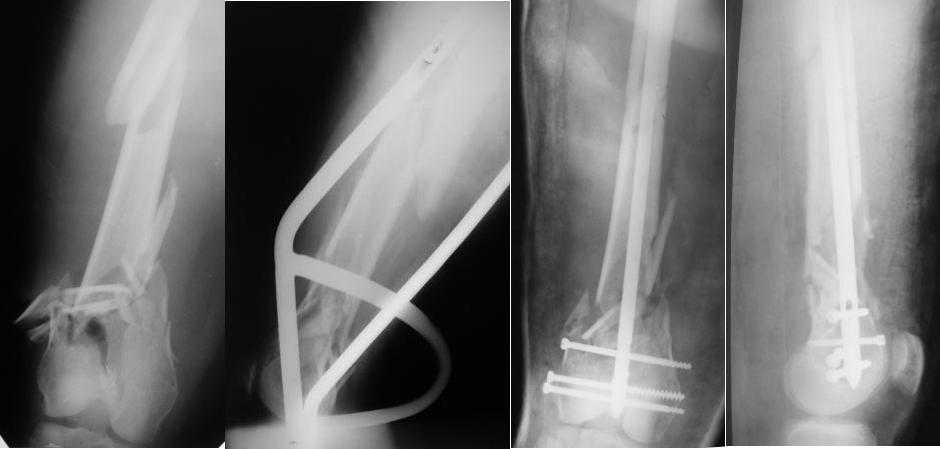

Приносим извенения за недостаток информации. Выкладываю все снимки. Стержень фирмы НПО ДЕОСТ(г.Пущино-на-оке)

Больная госпитализирована с тяжелой сочетанной травмой. Плюсом к перелому бедра имеется разрыв связок коленного сустава.